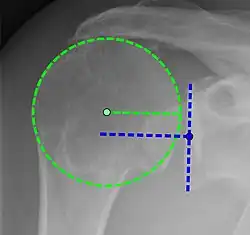

Xray

X-ray projectional radiography cannot directly reveal tears of the rotator cuff, a 'soft tissue', and consequently, normal X-rays cannot exclude a damaged cuff. However, indirect evidence of pathology may be seen in instances where one or more of the tendons has undergone degenerative calcification (calcific tendinitis). The humeral head may migrate upward (high-riding humeral head) secondary to tears of the infraspinatus, or combined tears of the supraspinatus and infraspinatus.[51] The migration can be measured by the distance between:

- A line crossing the center of a line between the superior and inferior rims of the glenoid articular surface (blue in image).

- The center of a "best-fit" circle positioned over the humeral articular surface (green in image)

Normally, the former is positioned inferiorly to the latter, and a reversal therefore indicates a rotator cuff tear.[51] Prolonged contact between a high-riding humeral head and the acromion above it may lead to X-ray findings of wear on the humeral head and acromion; secondary degenerative arthritis of the glenohumeral joint (the ball and socket joint of the shoulder), called cuff arthropathy, may follow.[50] Incidental X-ray findings of bone spurs at the adjacent acromioclavicular joint may show a bone spur growing from the outer edge of the clavicle downward toward the rotator cuff. Spurs may also be seen on the underside of the acromion, once thought to cause direct fraying of the rotator cuff from contact friction, a concept currently regarded as controversial.